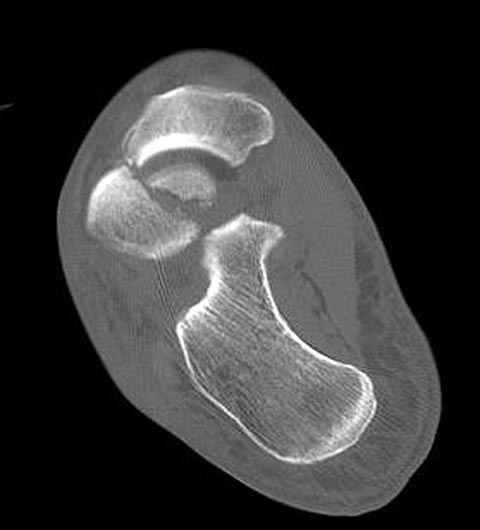

За пару недель насчитал 5 больных с переломом таранной кости, из них двое с двусторонним повреждением.

Из-за отека на стопе тактика лечения у всех была

одинаковая: временная наружная фиксация до спадения отека, при изолированных переломах они выписывались домой и через дней 7 госпитализировались на оперативное лечение.

Примеры на снимке...